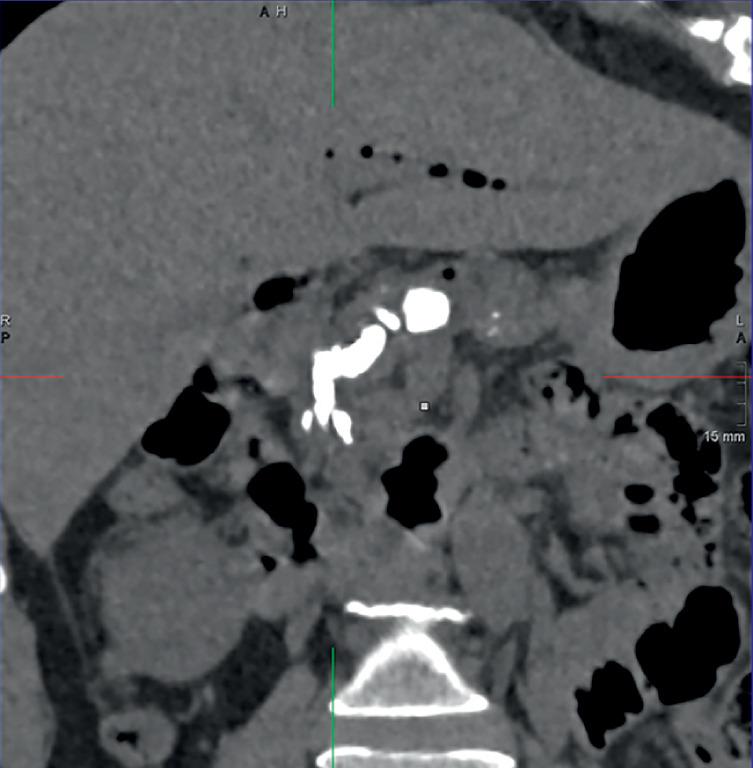

Multiple pancreaticobiliary fistulas combined with acute necrotizing pancreatitis: a rare complication of pancreatic extracorporeal shock wave lithotripsy.

摘要